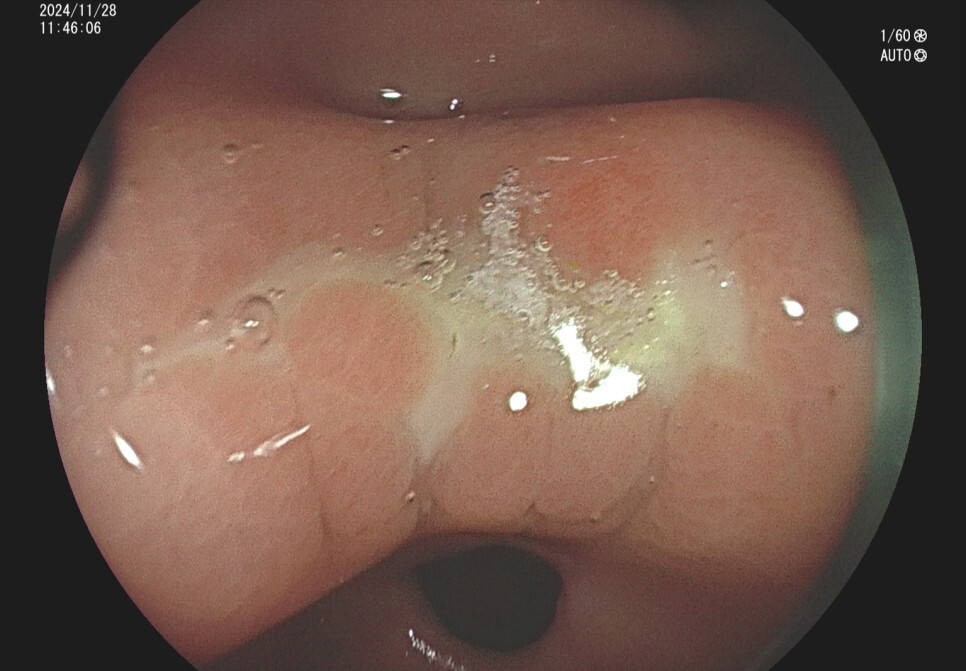

위궤양의 내시경 소견 증례입니다.

사례 1.57세 남성, 기상 후 입이 쓴 증상 주소로 내원

사례2. 36세 남성, 식후 속쓰림 증상으로 내원

과거 위내시경상 위궤양 의심 소견있었으나 치료 안하고 방치, 헬리코박터위염 확인됨.

사례 3. 35세 여자, 공복의 속쓰림 주소로 내원

사례4. 29세 여자, 속쓰림과 어지러움 주소로 내원